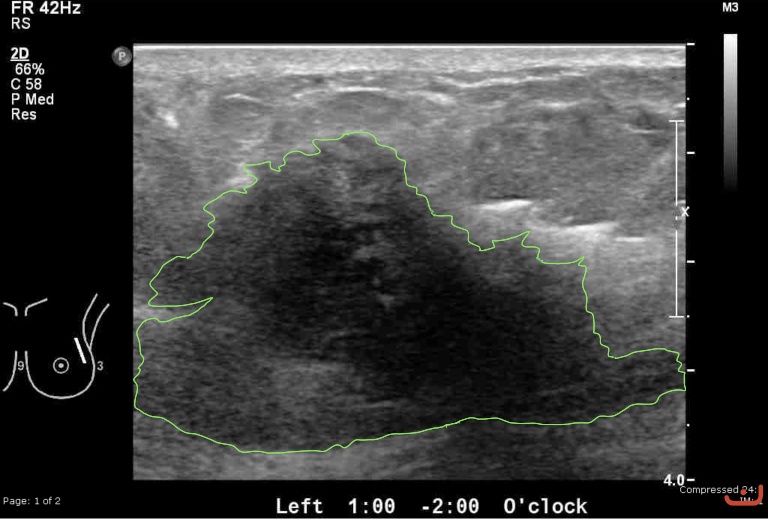

Malignant solid mass

Friday, 22 May 2015

197.84 KB (768 x 519 px)